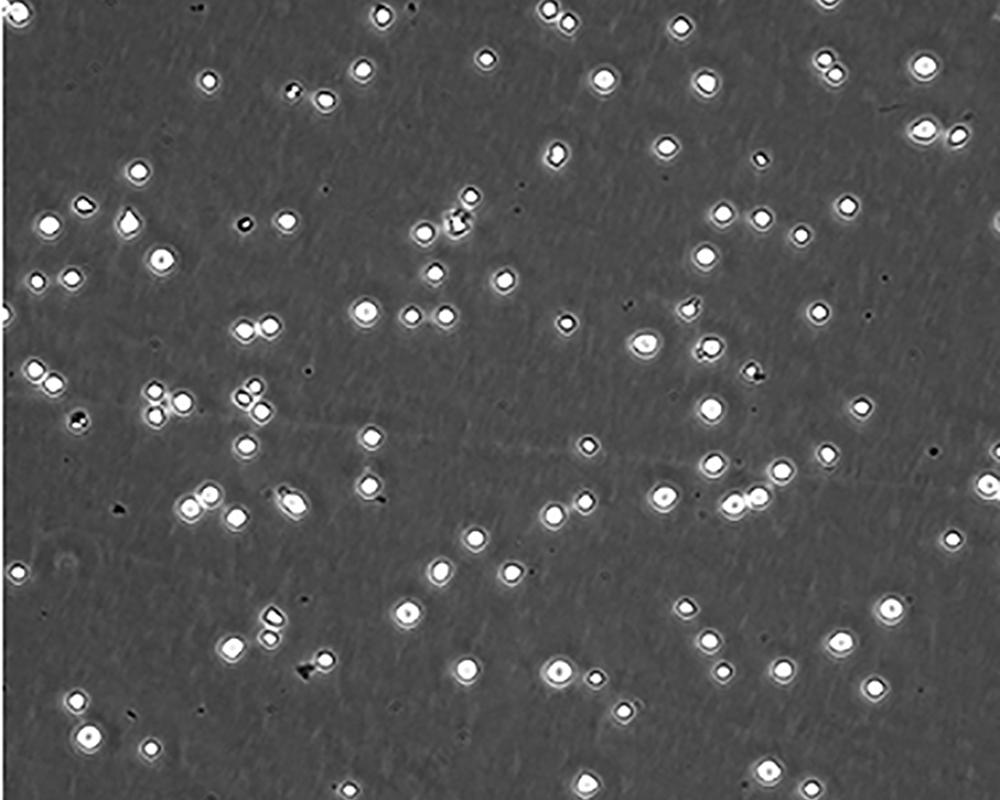

中文名稱(chēng) 人急性淋巴細(xì)胞白血病細(xì)胞

組織來(lái)源 急性T淋巴細(xì)胞白血病;女性

生長(zhǎng)特性 suspension

形態(tài)特征 lymphoblast

細(xì)胞描述 CEM/C1是人T細(xì)胞白血病細(xì)胞株CCRF-CEM(見(jiàn)ATCC CCL-119)具有喜樹(shù)堿抗性的衍生株。1991年細(xì)胞株選擇并亞克隆了對(duì)CPT的抗性。細(xì)胞表現(xiàn)出對(duì)CPT類(lèi)似物水溶性的托泊替康和非水溶性的9-氨基-CPT及10,11-亞甲二氧基-CPT具有交叉抗性。CEM/C1細(xì)胞對(duì)CPT的敏感性較母系CEM細(xì)胞低31倍。CEM/C1細(xì)胞表現(xiàn)非典型的多藥抗性和轉(zhuǎn)換拓補(bǔ)異構(gòu)酶I催化活性。對(duì)CPT的抗性維持6個(gè)月以上。